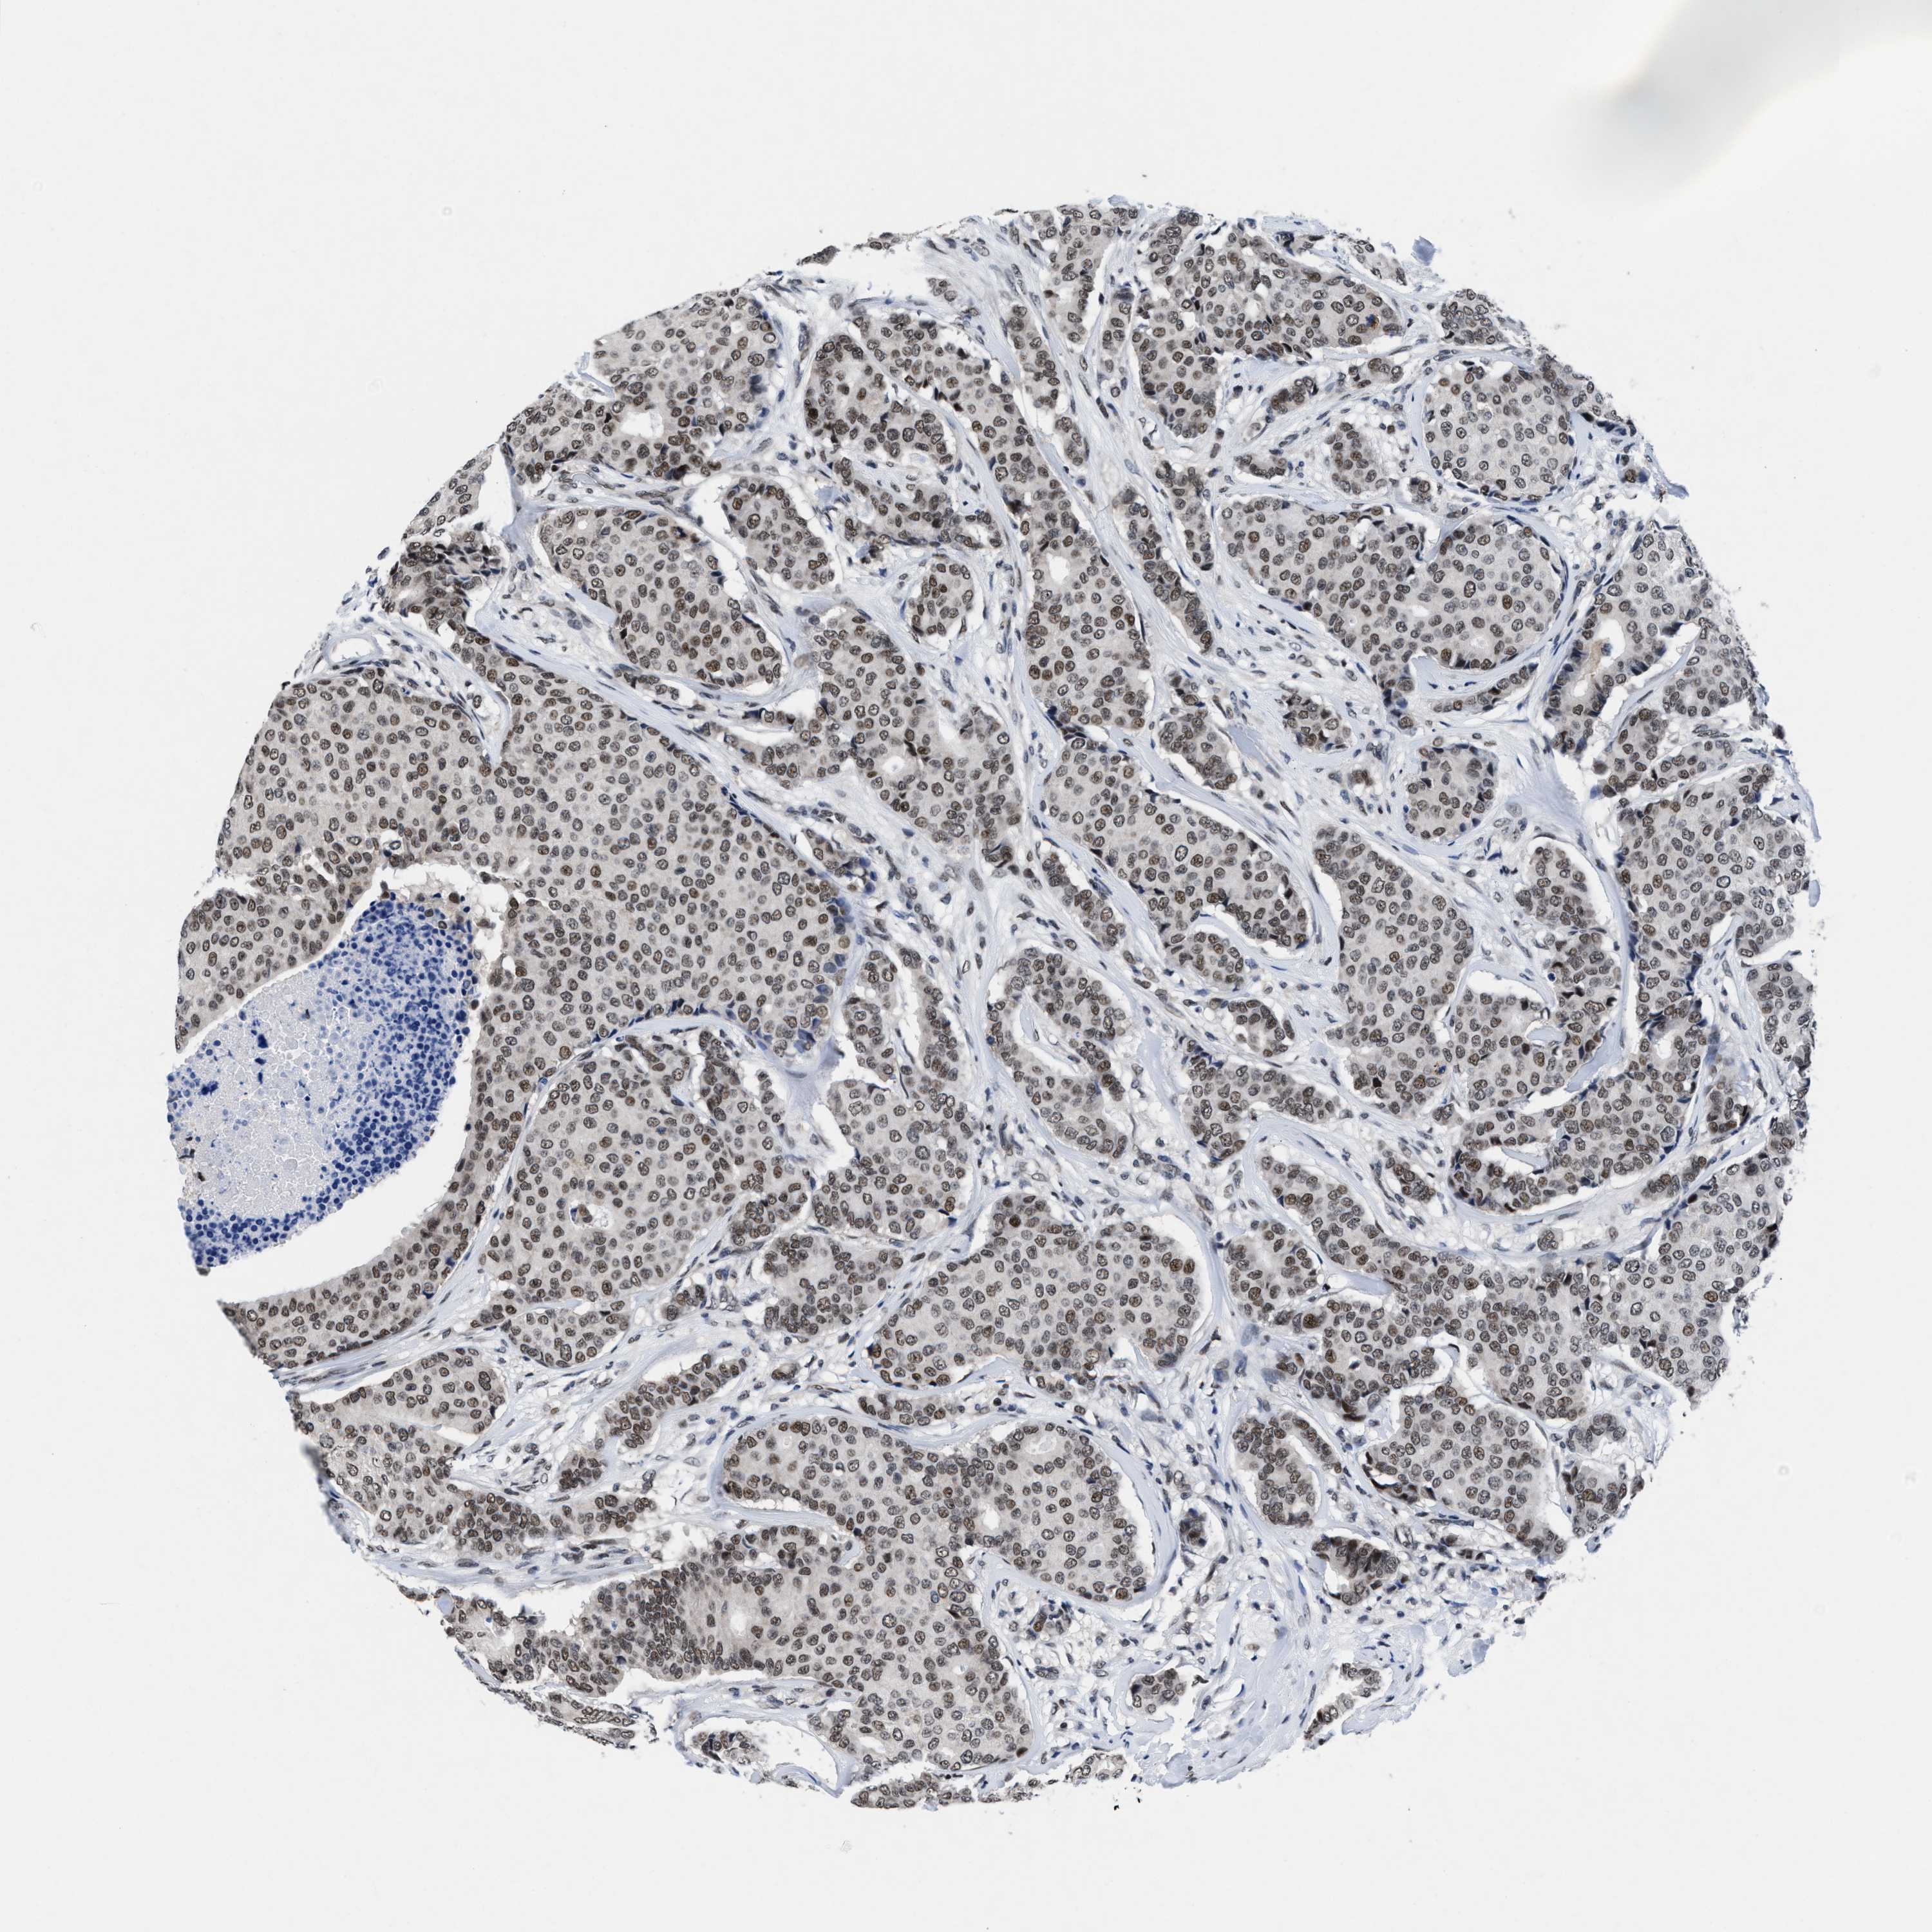

BRCA TCGA BRCA VALIDATION PROTEIN EXPRESSION